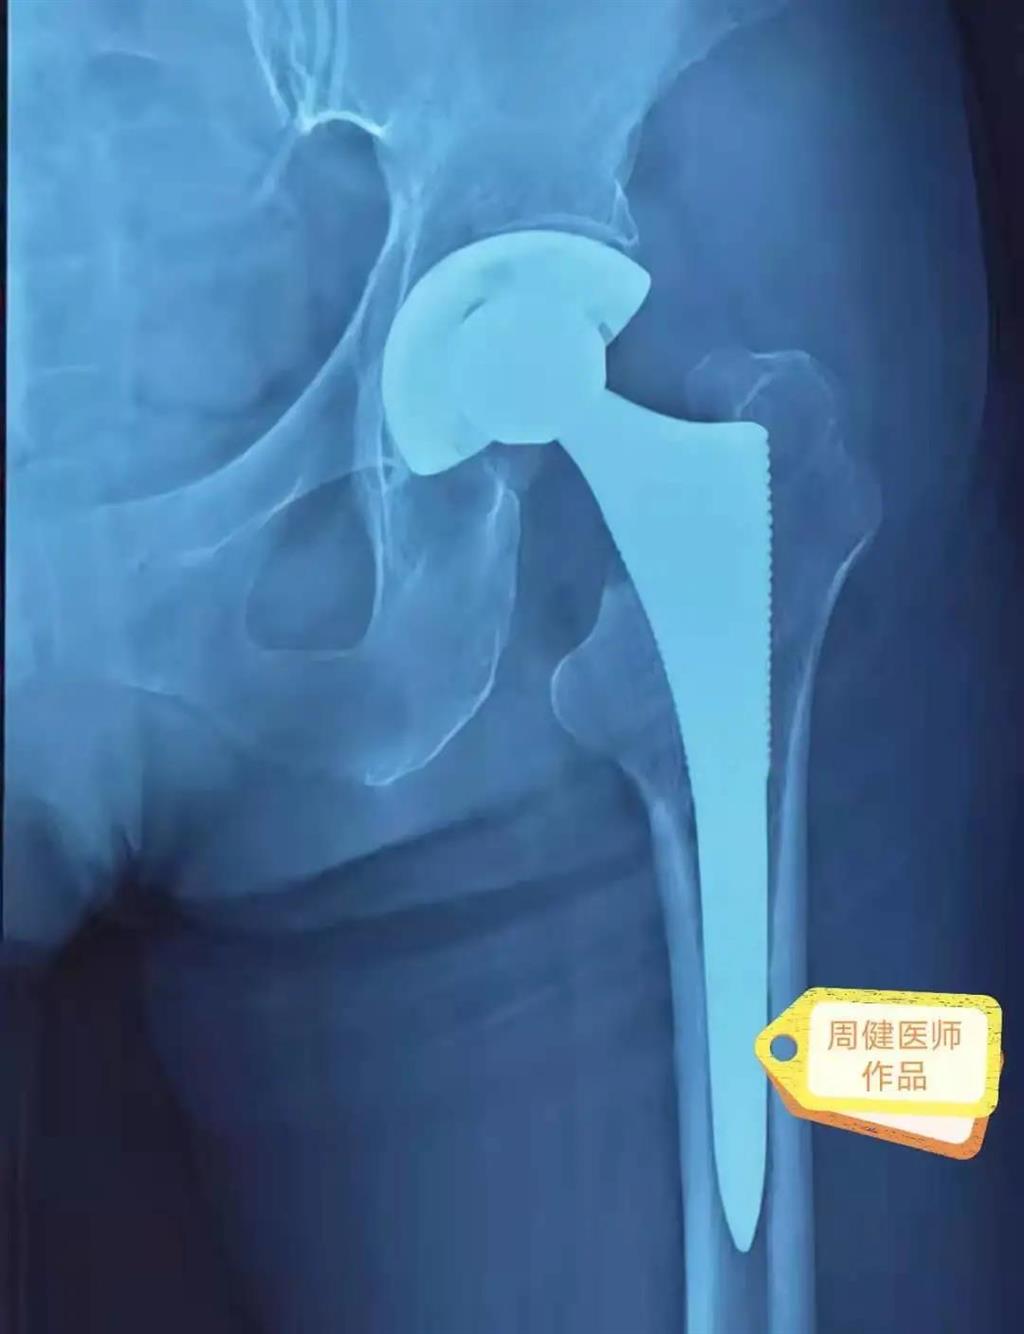

6月30日的“關(guān)節(jié)置換術(shù)”,患者是一位上了年紀(jì)的老人,苦于病痛折磨多年的他四處“求醫(yī)問(wèn)藥”,最后在多位專家醫(yī)師及病友地力薦下選擇了和平國(guó)際醫(yī)院,在醫(yī)師團(tuán)隊(duì)“偷天換日”般的手術(shù)后,老人成功告別了苦纏多年的病痛。

周健說(shuō),這場(chǎng)“關(guān)節(jié)置換術(shù)”對(duì)于他們團(tuán)隊(duì)而言其實(shí)算是比較普通的手術(shù),因?yàn)樽鲞^(guò)很多同類的手術(shù),成功案例繁多,因此在手術(shù)操作上有較多地實(shí)操經(jīng)驗(yàn)。“不過(guò)話雖如此,作為醫(yī)生我們對(duì)于每一場(chǎng)手術(shù)都會(huì)全力以赴,這是為醫(yī)者的職責(zé)也是義務(wù)。”